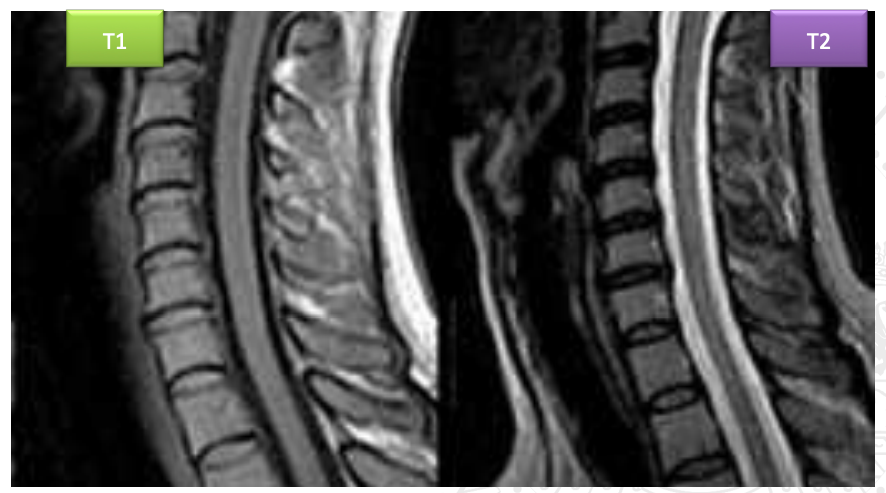

Imagen potenciada en T1 – Tiempo de relajación longitudinal

- brilla la Grasa

Imagen potenciada en T2 – Tiempo de relajación transversal

Brilla el líquido

La grasa tiene un T1 muy corto, son los primeros nucleos que vuelven al estadío normal, liberan mucha energía se ve BLANCO

El LCR tiene un T1 muy largo: NEGRO

IMPORTANTE: En cada secuencia (T1, T2, etc.) la escala de grises cambia por completo y no tiene nada que ver con las densidades radiológicas.